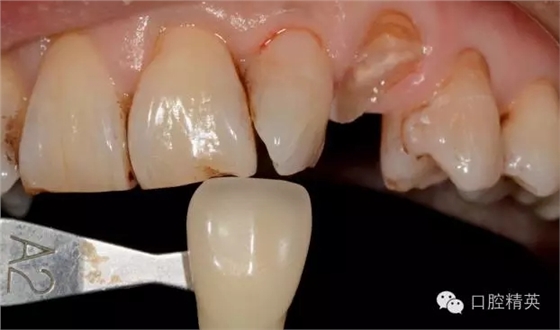

圖4修復(fù)前選色: